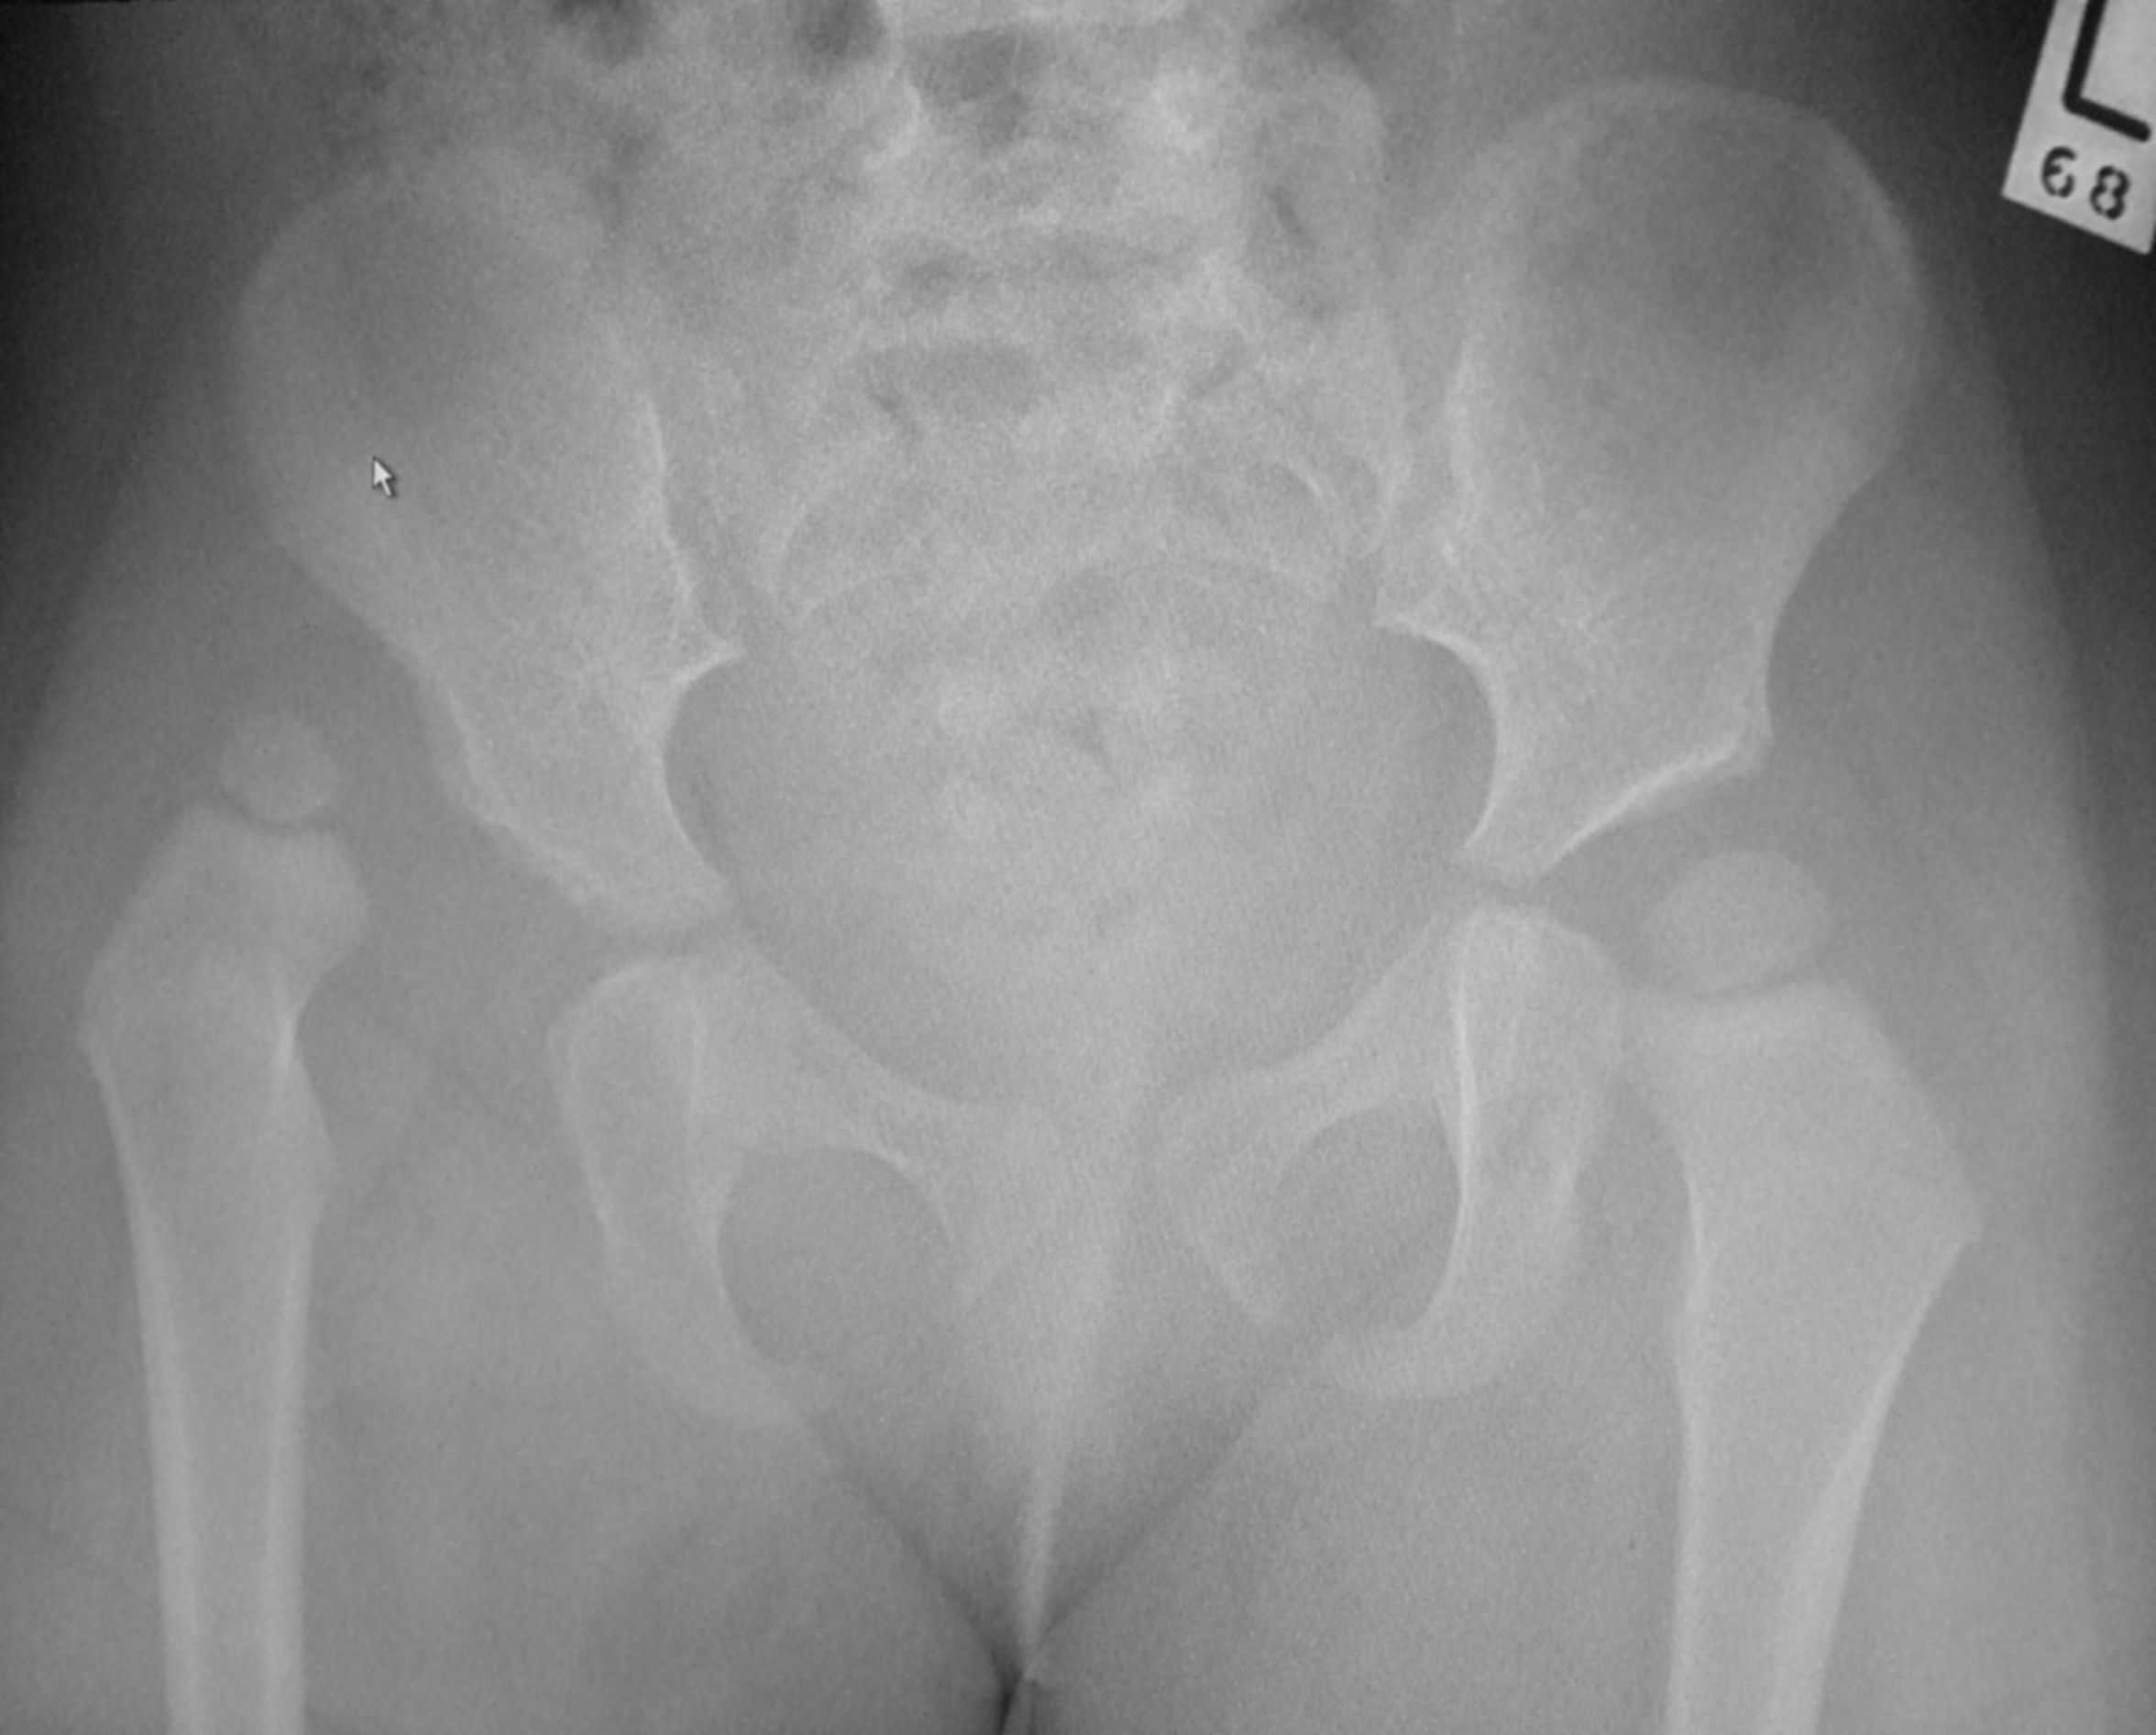

고관절 이형성증 엑스레이 사진도 참고할 수 있다. 골반 X-레이는 고관절 이형성증을 진단하거나 모니터링하거나, 다른 선천성 질환 또는 골종양을 평가하는 데 여전히 자주 사용된다.[45]

골반 X-레이는 고관절 이형성증을 진단하거나 모니터링하거나, 다른 선천성 질환 또는 골종양을 평가하는 데 여전히 자주 사용된다.[45]